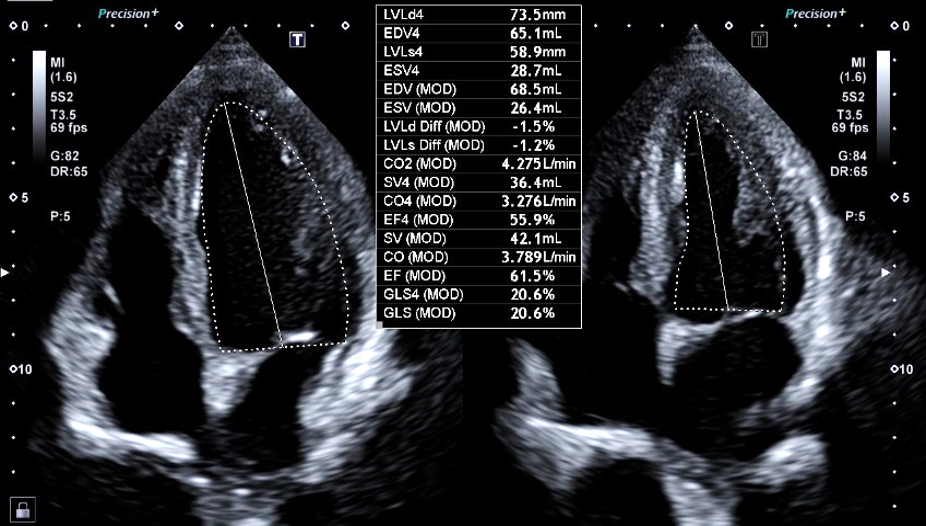

その中で心臓の動き(壁運動評価)は、心エコー検査の中でも、熟練が必要だと言われてます。また読影する人によりばらつきが生じることもあります。

AI技術を用いて自動でEF(左室駆出率)を算出する機能と同時に、詳細な壁運動の指標をカラーマップで提示でき、収縮のタイミングもグラフで確認可能となり詳細な解析が可能となります。

2D Wall Motion Tracking